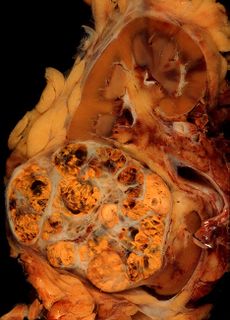

سرطانة الخلايا الكلوية (أسفل اليسار) في عينة مأخوذة من كلية.